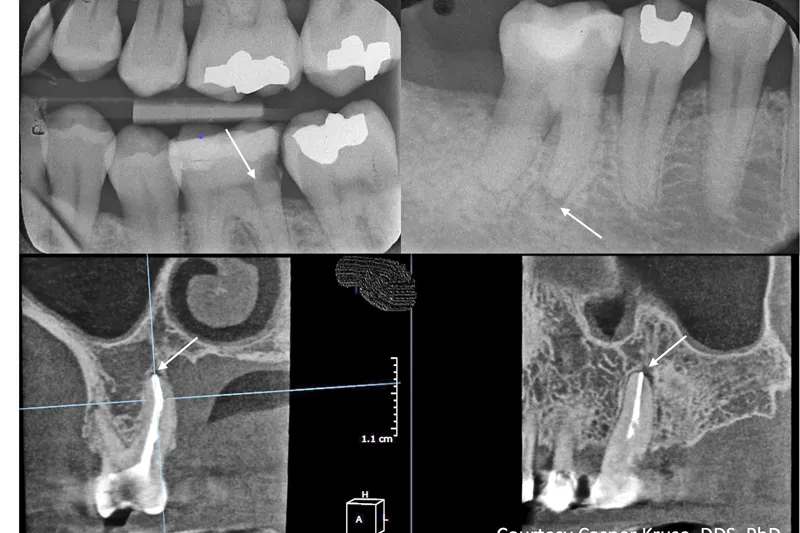

Endodontisk diagnostik fokuserer hovedsagelig på identifikation af infektionsbetingede inflammationstilstande i pulpa og de periapikale væv. Anamnese, aktuelle og tidligere symptomer, kliniske observationer og tests samt radiologiske fund er de faktorer, der almindeligvis leder frem til diagnosen, men evidensen for en korrelation mellem specifikke anamnestiske, kliniske fund og pulpas sande tilstand er beskeden, og der er ikke klar konsensus om de diagnostiske kriterier. Nye og forbedrede metoder til vital pulpabehandling gør det muligt at bevare pulpas vitalitet i flere tilfælde i dag end tidligere, og dermed øges behovet for valide metoder til sikker identifikation af pulpas tilstand. En korrekt diagnose er en forudsætning for sufficient behandling, og pålideligheden af aktuelle og fremtidige diagnostiske tegn og tests bør undersøges i studier af høj kvalitet. I dag anvendes der forskellige diagnostiske terminologier i de nordiske lande, men de er dog sædvanligvis i et vist omfang baseret på ICD-10. Det ville være gavnligt for både tandlæger og patienter, hvis der kunne opnås enighed om diagnostiske termer på baggrund af klare og operationaliserede kliniske og datafunderede diagnostiske kriterier.

Endodontic diagnostics is mainly focused on identifying pulpal and periapical infection-driven inflammation. History of events, previous and current symptoms, clinical observations and tests, and radiographic examination findings are the factors commonly used to derive the diagnosis, but the evidence for the correlation of specific anamnestic or clinical findings with the true state of the pulp is scarce, and clear consensus for diagnostic criteria is lacking. New and improved methods for vital pulp treatment enables preservation of pulp vitality to a greater extent today than historically, with increasing demands of valid methods for reliable identification of the state of the pulp. A correct diagnosis is a prerequisite for appropriate management, and the accuracy of current and future diagnostic cues and tests should be examined in high-quality studies. Today, diagnostic terms vary between the Nordic countries but are usually to some extent based on ICD-10. Mutually agreed diagnostic terms based on clear and operationalized clinical and data-driven diagnostic criteria would be helpful for the dentist and benefit the patients.